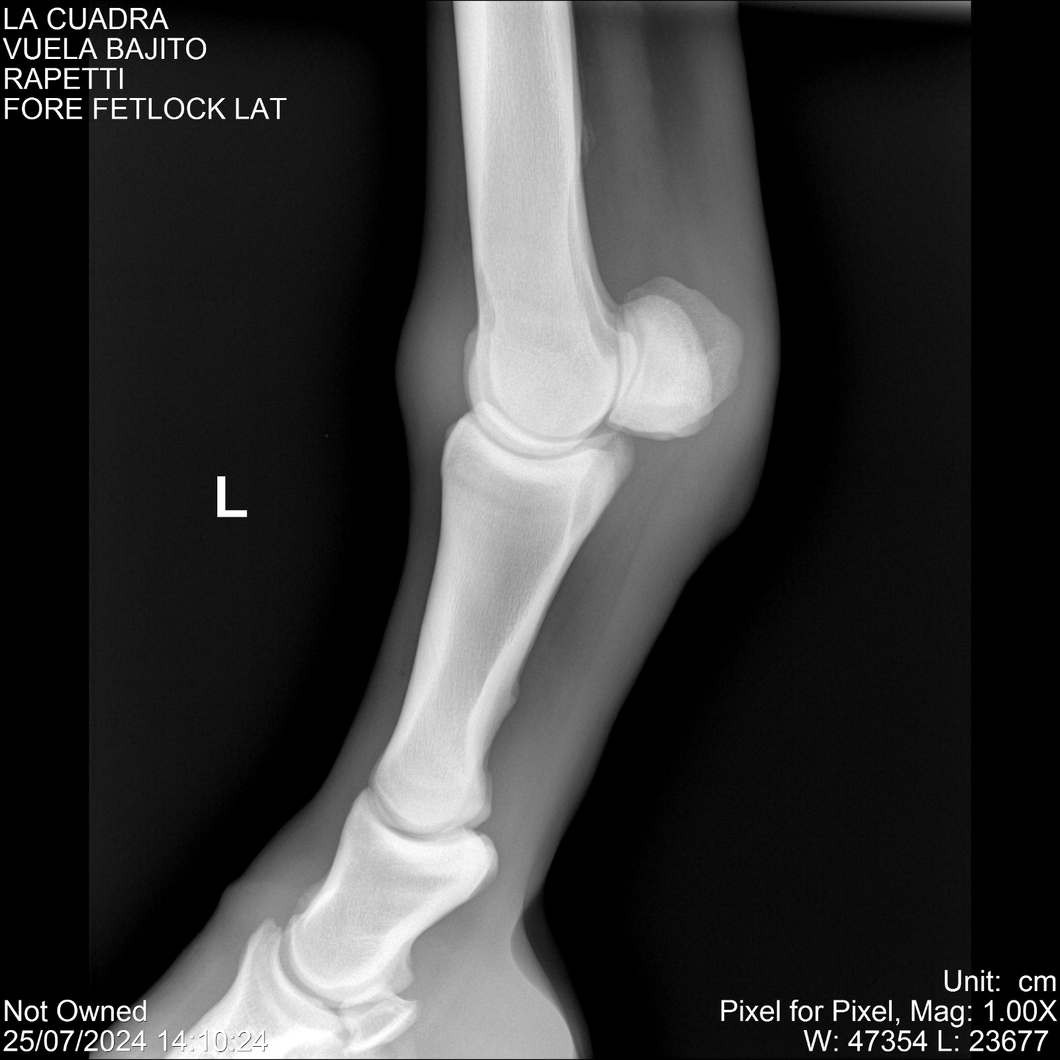

LOTE 16, VUELA BAJITO Lote Anterior Volver al remate Lote Siguiente Ficha Contacto Montevideo - Ficha del Lote Identificador: #284451 Categoría: Yeguarizos Montevideo - 77 Visualizaciones ClicData Contacto Empresa: Abelenda N. R., Walter Hugo Nombre*: Teléfono* : E-mail* : Mensaje Enviar Registrese gratis Este contenido Exclusivo está disponible sólo para usuarios registrados Ingresar